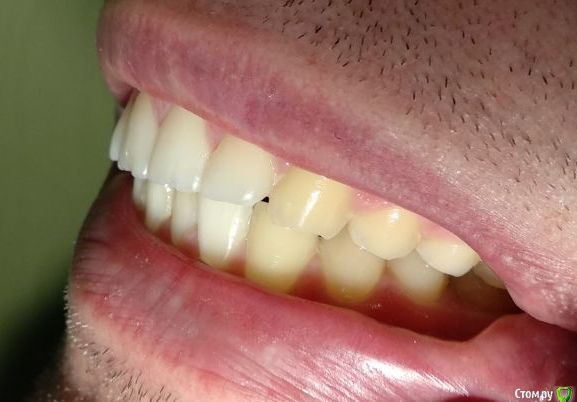

Нормально вылечены каналы. Покажите фото сомкнутыми зубами

Сделал несколько фотографий, тк не совсем понял с какого ракурса делать фото с сомкнутыми зубами.